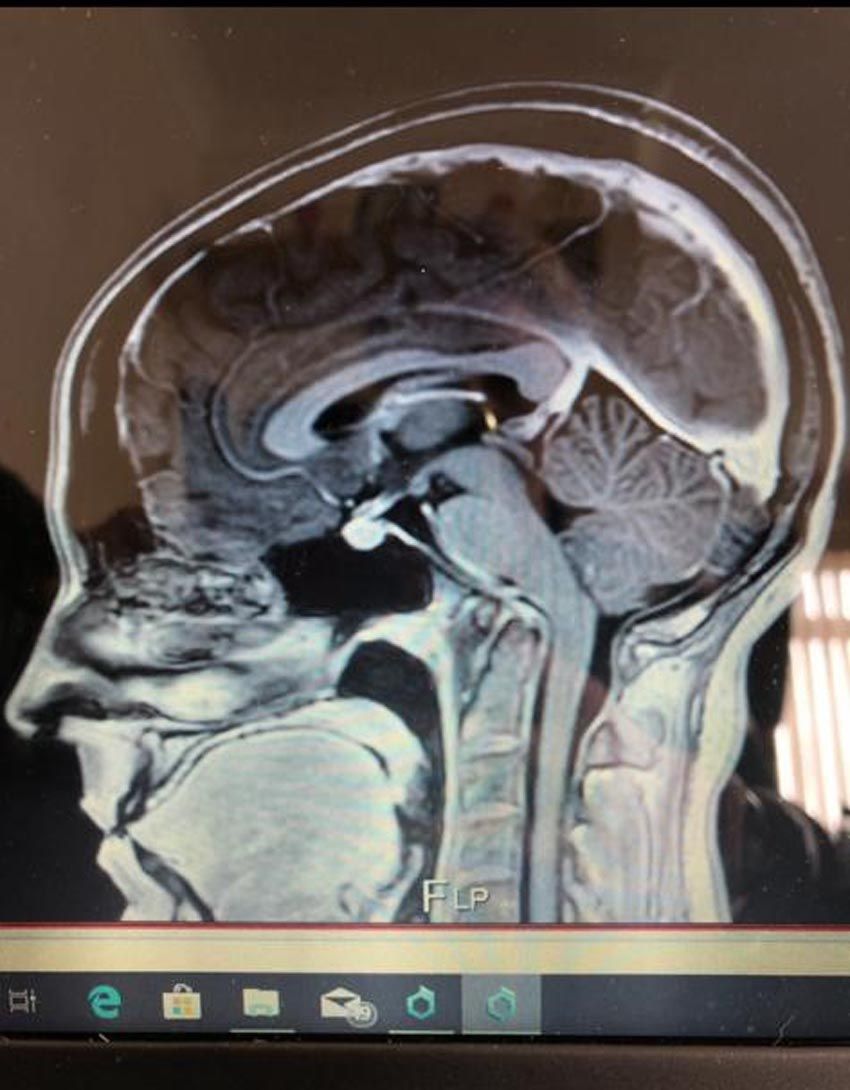

Seeing a private endocrinologist – a specialist treating problems with hormones – in the autumn of 2018, she had an MRI scan, which came back clear.

And in May 2019, a neurologist also diagnosed her with Chiari malformation, a non-life threatening condition, where the lower part of the brain pushes down into the spinal canal, according to the NHS.

“I posted my MRI scan in a Chiari malformation Facebook group and people were commenting, saying Chiari was the least of my problems," Rachel recalled."

Then paying £1,300 ($1,570) for a private upright MRI scan, Rachel asked for the images be sent to Dr. Gilete, a top neurosurgeon she had found via a Facebook group in Barcelona, Spain – one of only three experts worldwide dealing with minimal invasive spinal surgery techniques.

Having assessed the MRI and carried out a detailed questionnaire, he added to her diagnosis atlantoaxial instability – where the vertebrae holding her skull in place become unstable and dislocated, hydrocephalus, which is an accumulation of cerebrospinal fluid within the brain, scoliosis, a curvature of the spine, and cervical medullary syndrome, which is caused by brain stem compression.